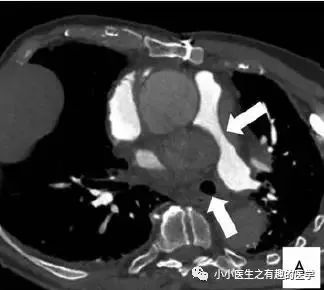

法兰西报道的一个患者。

这么大一个血栓!

好大的一条血栓!然而,最终做了手术,病理如下:

五颜六色的,好好看啊。然而,this is 肺动脉内膜肉瘤。仔细看看,不对。

充盈缺损的地方,密度不均匀,并且有强化,血栓里面没有血管,一般不会强化,所以有可能是肿瘤。